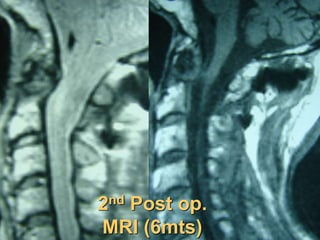

2nd Post op.

CT scan

MRI (6mts)

MRI